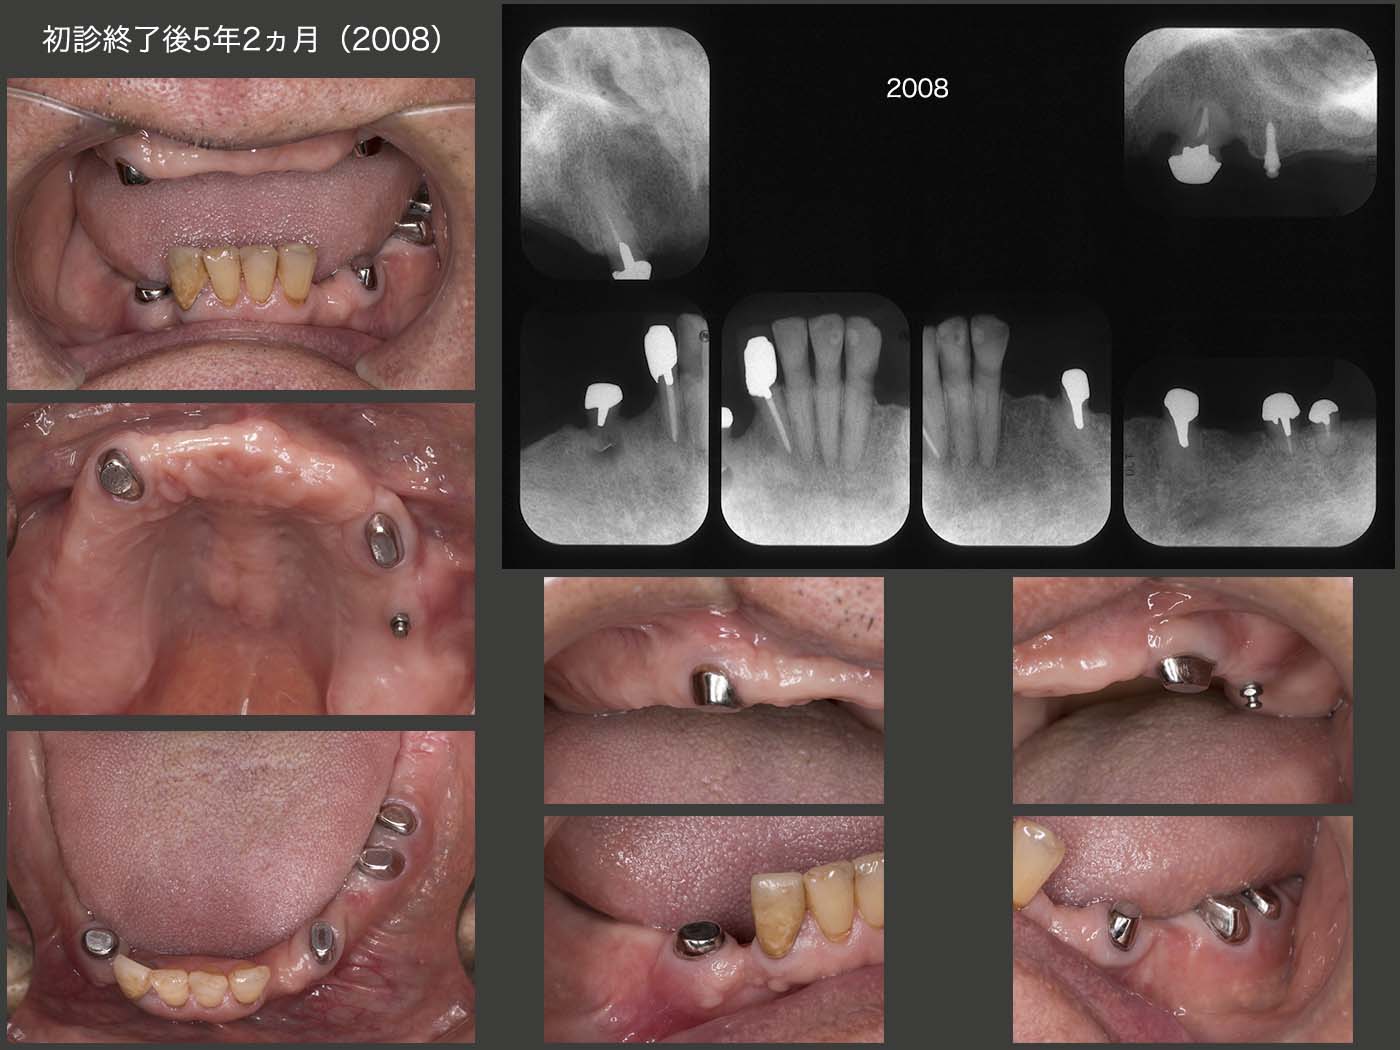

初診終了後5年2ヵ月,2020年8月の状態.右上6の口蓋根を移植した右下4の歯に,歯周ポケットが頰側で8mm認められた.実は18年7月のリコール時から右下4にフィステルが生じていた.その時歯周ポケットはなく,19年7月の時に6mm存在した.移植した際,根尖部をスーパーボンドで封鎖したが,不十分であったかもしれない.

その他は特に問題ない.

義歯はまったく問題なく経過している.支台歯根面を開放したことは,根面マージン部の2次カリエス予防にとって,十分意義がある.

最後のあがきとして,右下4の歯周ポケットに,歯間ブラシを挿入するようにお願いした.